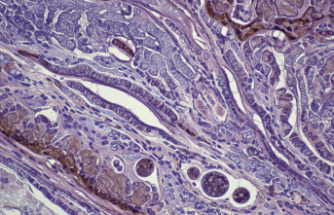

Hastalık sadece ciltle sınırlı kalmıyor maalesef. Fibröz displazi (kemik dokusunun bozulması) dediğimiz durum kemikleri cam gibi kırılgan hale getirebiliyor. Aslında bakarsınız vücut, sağlam kemik yerine yumuşak bir doku üretmeyi tercih ediyor o an. Bu durum yüz hatlarında asimetriye veya bacaklarda eğriliğe yol açıyor. Acaba geçer mi diye beklemek süreci zorlaştırıyor çoğu zaman.

• Fibröz Displazi: Sağlıklı kemik dokusunun yerini skar benzeri (yara izi gibi) lifli dokunun alması durumudur.